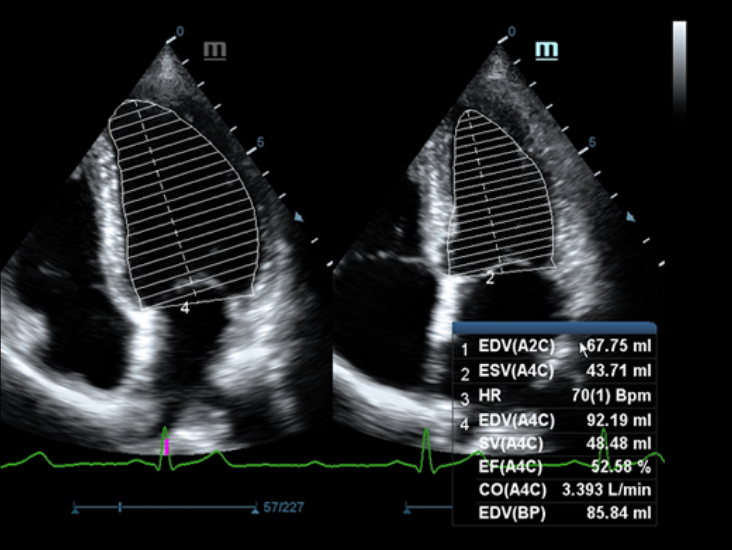

Sobre la base de un profundo conocimiento de las necesidades del cliente, el DC-60?ECHO con X-Insight estå dise?ado para brindar alta eficiencia con imågenes precisas, lo que se ve potenciado con eXpress Clarity (claridad exprés), eXceptional Intelligence (inteligencia excepcional) y eXceeding Experience (experiencia extraordinaria).

eXceeding Experience

Experiencia con alta productividad